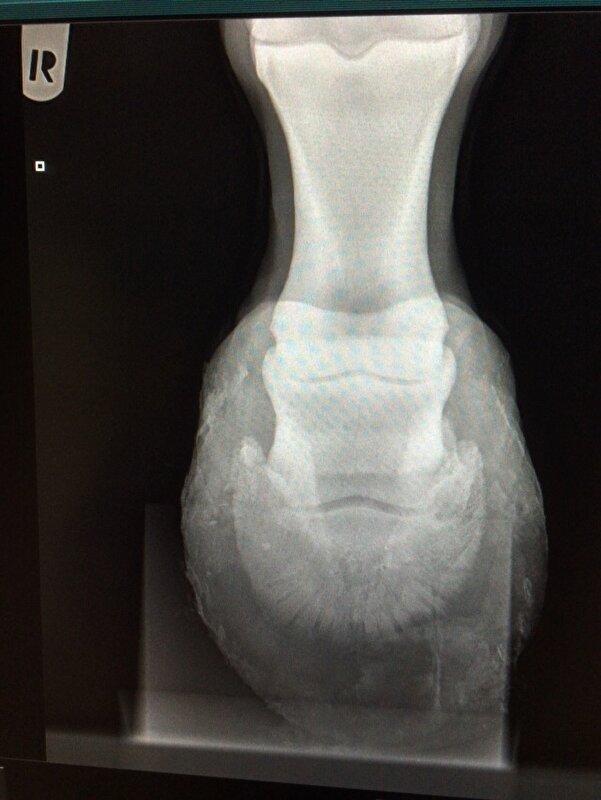

Dus volgens mij werkt het. nuvel schreef:Had gister gebeld maar er was nog niks klaar. Net heb ik de foto's gekregen van beide voorvoeten en het ziet er niet zo goed uit. Beide hoefbenen zijn gekanteld. De ene als je er voor staat is het het linker voorbeen daar komt het hoefbeen bijna door de zool. Als je er voor staat het rechter voorbeen heeft nog een cm voor hij door de zool komt.

Zal straks de rontgenfoto's en foto van het paard hier plaatsen. Ga ze nu eerst naar de kliniek sturen want wil er voor vechten. Dit paard is te sterk en te vrolijk om nu de handdoek in de ring te gooien. Ze staat op dubbele pijnstiller om nu niet te hoeven lijden.